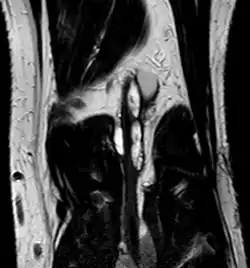

Klinisch stellt sich das Krankheitsbild mit einer wechselnden Beschwerdesymptomatik dar, die eine Abhängigkeit von der Belastung des betroffenen Kniegelenks zeigt.[13] Die Durchblutungsstörungen können dabei unter Umständen im Sinne eines Provokationstestes durch Beugung im Kniegelenk ausgelöst oder verstärkt werden.[4][14] Als bildgebende Diagnostik wird neben dem Ultraschall mit Duplexsonographie die Computertomographie und spezifischer und ohne Strahlenbelastung die Magnetresonanztomographie eingesetzt.[4] Diese zeigt oft gekammerte, runde bis länglich ovale Zysten in der Gefäßwand. Eventuell vorhandene zusätzliche Ganglien am Kniegelenk können in der gleichen Untersuchung erfasst werden. Die Zysten sind signalintens in T2-gewichteten, signalarm in T1-gewichteten Bildern und nehmen kein Kontrastmittel auf. Die Angiographie zeigt bei ansonsten in der Regel unauffälligen Gefäßen eine umschriebene, scharf begrenzte, bogige Kontrastmittelaussparung, die je nach Ausdehnung der Zysten auch mehrfach und von beiden Seiten vorkommen kann. Man spricht vom Scimitar-Zeichen (Scimitar = Krummsäbel).[8] Dieser ursprünglich in der konventionellen Angiographie verwendete Begriff wird heute auch in der Magnetresonanztomographie, insbesondere in der MRA gebraucht.